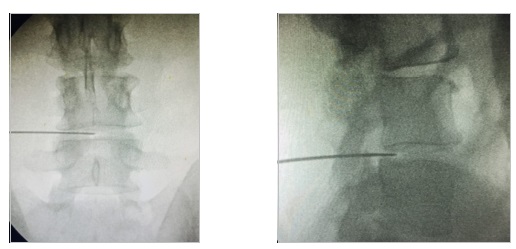

Η επέμβαση γίνεται κάτω από συνεχή ακτινοσκοπική καθοδήγηση με τον ασθενή σε πρηνή θέση και ήπια καταστολή. Εισάγεται μια ειδική βελόνη στον δίσκο και μέσω αυτής εισέρχεται ένας ειδικός καθετήρας που συνδέεται με τη γεννήτρια του μηχανήματος που χορηγεί την ενέργεια. η επερχόμενη μείωση της ενδοδισκικής πίεσης, προκαλεί την υποχώρηση της κήλης προς το κέντρο του δίσκου, μειώνοντας έτσι την πίεση της σύστοιχης νευρικής ρίζας. Σε μια επέμβαση δύναται να αντιμετωπισθούν έως και 3 επίπεδα δίσκου.

Η τεχνική εφαρμόζεται στην αυχενική μοίρα της σπονδυλικής στήλης με πρόσθια προσπέλαση και στην οσφυϊκή μοίρα με οπίσθια προσπέλαση, κάτω από ακτινοσκοπική καθοδήγηση και με χρήση σκιαγραφικής ουσίας για την απεικόνιση του δίσκου πριν την έναρξη της εξάχνωσης.